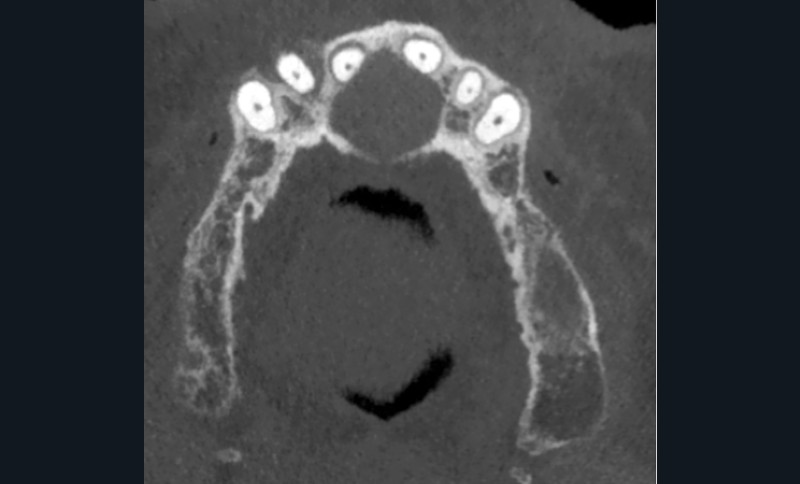

- Centré sur la ligne médiane de la portion antérieure du palais.

- Lésion ostéolytique radio-claire.

- Homogène et bien délimitée.

- Uni-loculaire (fig. 3), pouvant présenter un aspect caractéristique de « cœur de carte à jouer ».

- Diamètre moyen des lésions de 2 cm.